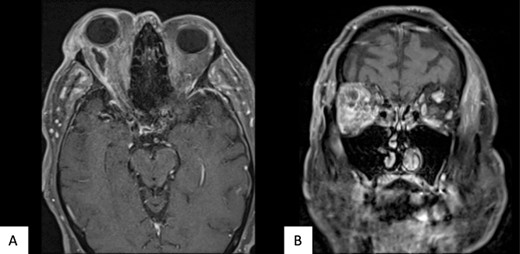

Preceding this presentation, magnetic resonance imaging (MRI) attributed his presenting features to an inflamed retroorbital congenital cystic structure, adjacent to the inferonasal aspect of the globe, accompanied by mild inflammatory changes in the surrounding orbital tissues. At the time, this was considered radiologically not infective (Fig. 1). He was afebrile, without raised inflammatory markers. Whilst pending further diagnostic opinion, a trial of oral steroids was given. He had clinically improved within the month of commencing treatment with reduced inflammation.

(A) T1 MR Orbits, and (B) T2 MR Orbits shows an intraconal mass measuring 16 × 8 × 15 mm in the inferonasal quadrant abutting the wall of the globe in the right orbit.